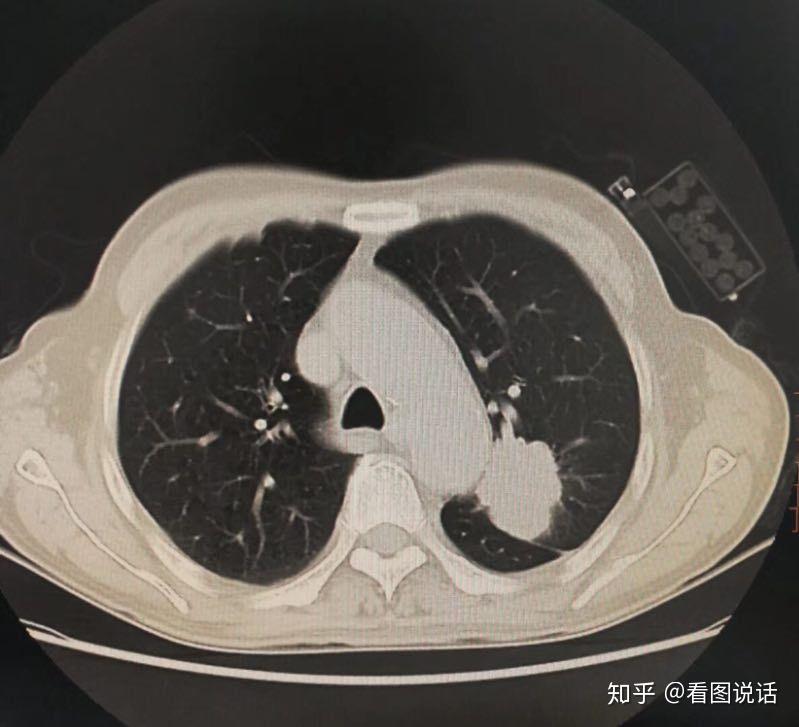

38岁男性,大量吸烟史,咯血,右侧胸痛半月余,伴消瘦,胸片右肺占位?